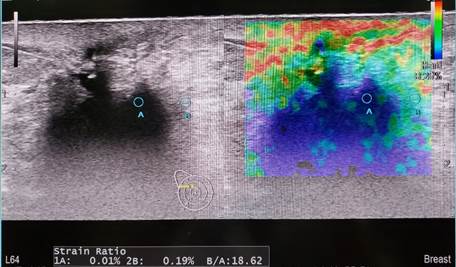

Siêu âm đàn hồi mô

Siêu âm đàn hồi mô (Elastography) là một ứng dụng khá mới của siêu âm chẩn đoán nhằm khảo sát đặc tính đàn hồi của mô trong cơ thể.